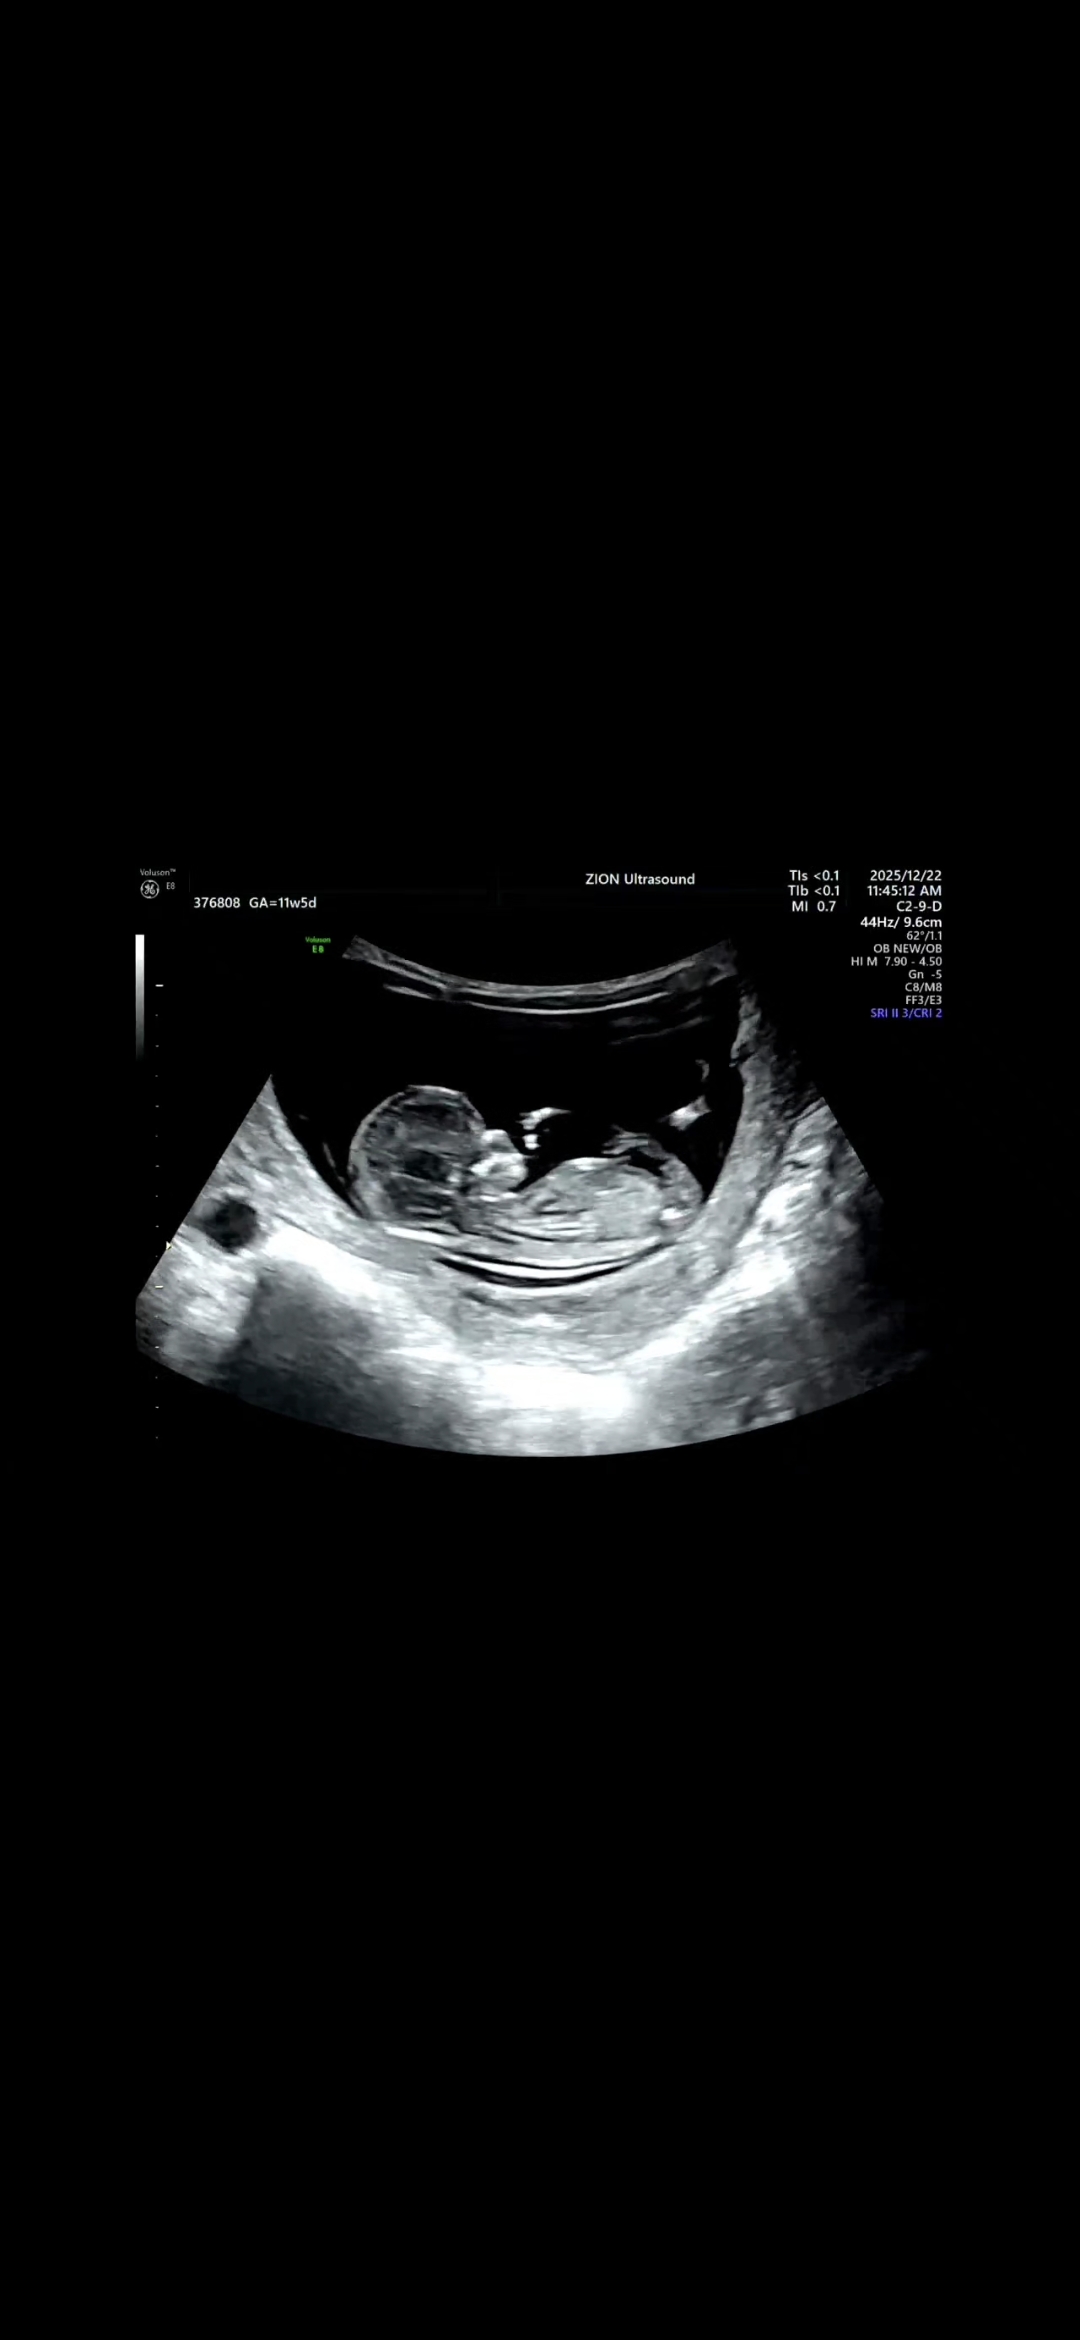

선배맘들 각도법 봐주세요ㅜㅜ!!

딸인가요 아들인가요ㅠㅠ!?